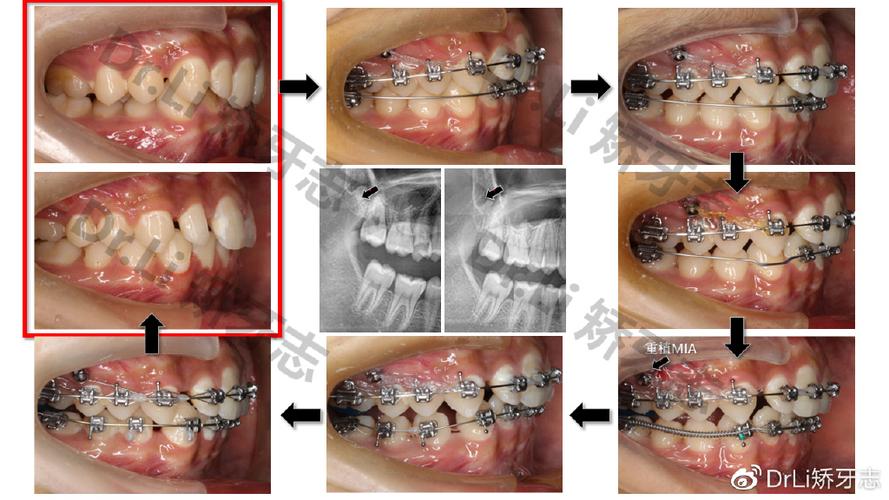

螺旋弹簧辅助远移(NiTi/Spiral Spring)

作用机制:在固定矫治器(如方丝弓、直丝弓矫治器)基础上,于磨牙与前牙间放置镍钛螺旋弹簧或不锈钢螺旋弹簧,利用弹簧展开产生的持续力推动磨牙远移,需通过腭杆、舌弓或种植支抗加强后牙支抗。

操作要点:弹簧力值控制在100-200g,每4周更换一次,移动过程中需用弓丝弯制“后倾弯”控制磨牙倾斜。

适应证:上下颌磨牙均可适用,尤其适用于牙弓轻度拥挤、需少量远移(<4mm)的病例。

优缺点:优点为操作简便,可精确控制力值;缺点是支抗要求高,若支抗不足易导致前牙前突,远移速度较慢(0.5-1mm/月)。